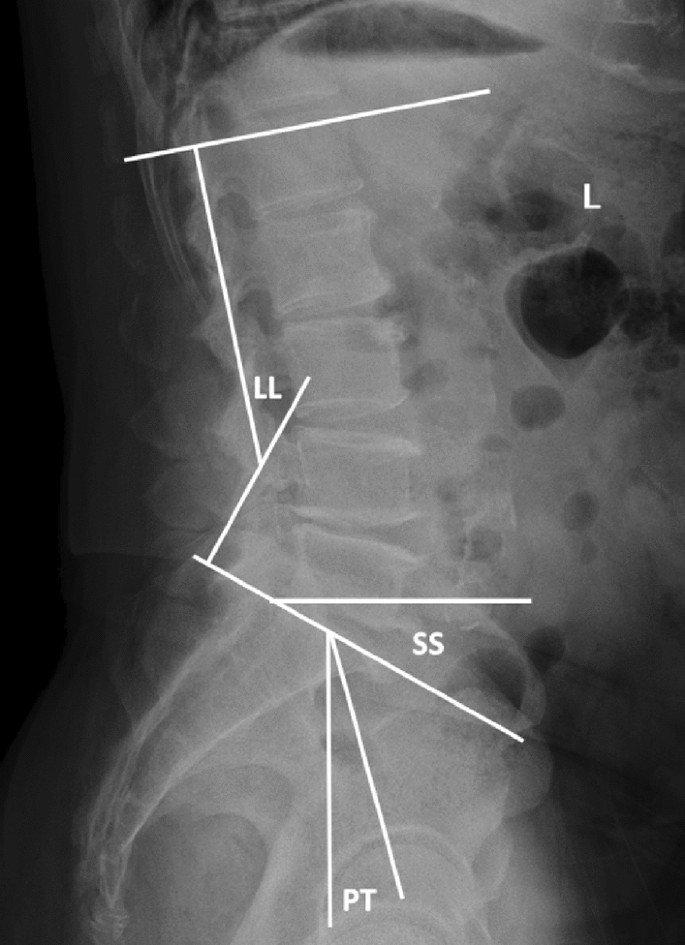

VAS and ODI scores of the two groups of patients were performed preoperatively, postoperatively and during the last follow-up to evaluate clinical efficacy. The operation time, intraoperative blood loss, surgical complications, hospitalization cost and hospital stay were recorded in the two groups. Lumbar spine X-ray and CT at the last follow-up were used to evaluate the existence of loose screws, bone cement leakage and failure of intervertebral fusion, LL, PT and SS (Fig. 1).

LL is defined as the angle between the end plate on L1 and the continuous end plate on S1.PT is defined as the angle between the connection and plumb line at the midpoint of the end plate and the center point of the femoral head on S1.SS is defined as the angle between the parallel and horizontal lines of the end plate on S1.